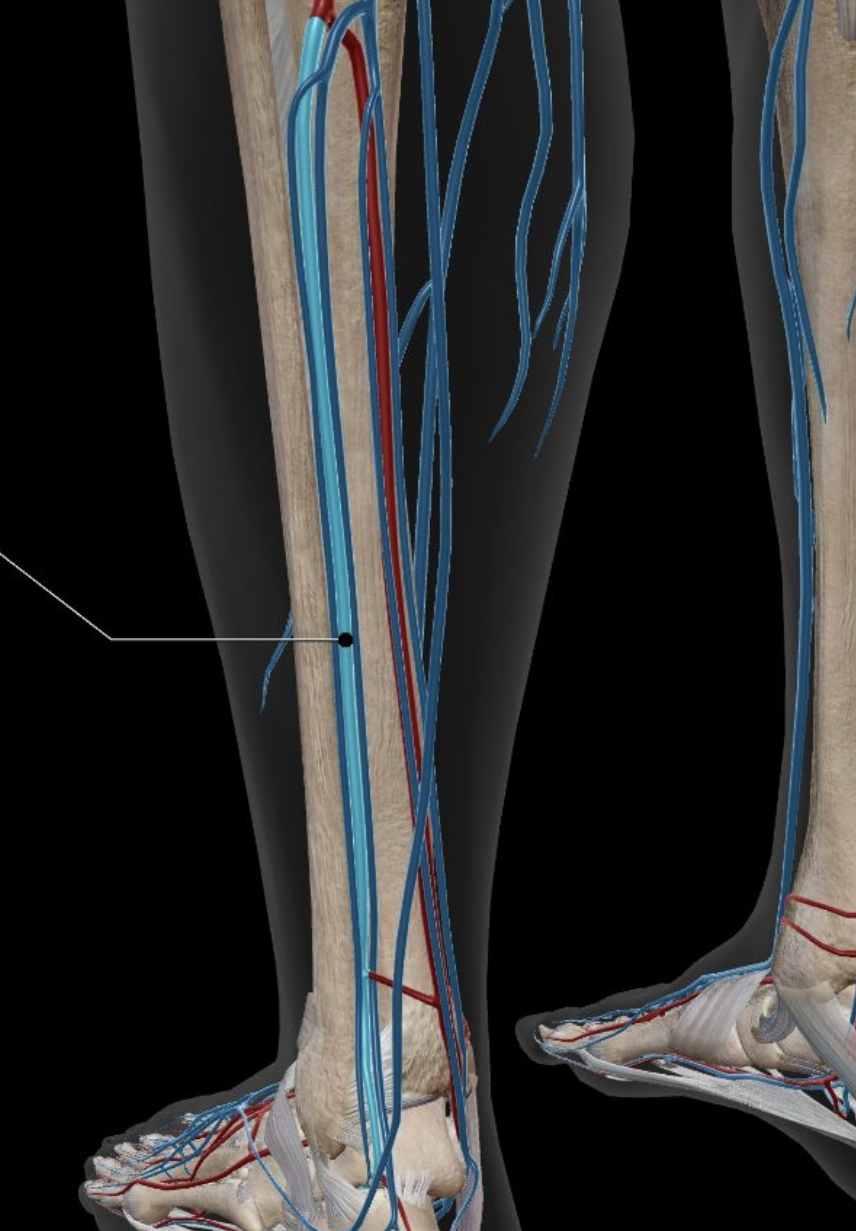

Anterior Tibial Artery

Posterior Tibial Artery

Anterior Tibial Vein

Posterior Tibial Vein

Great Saphenous Vein

Peroneal Artery